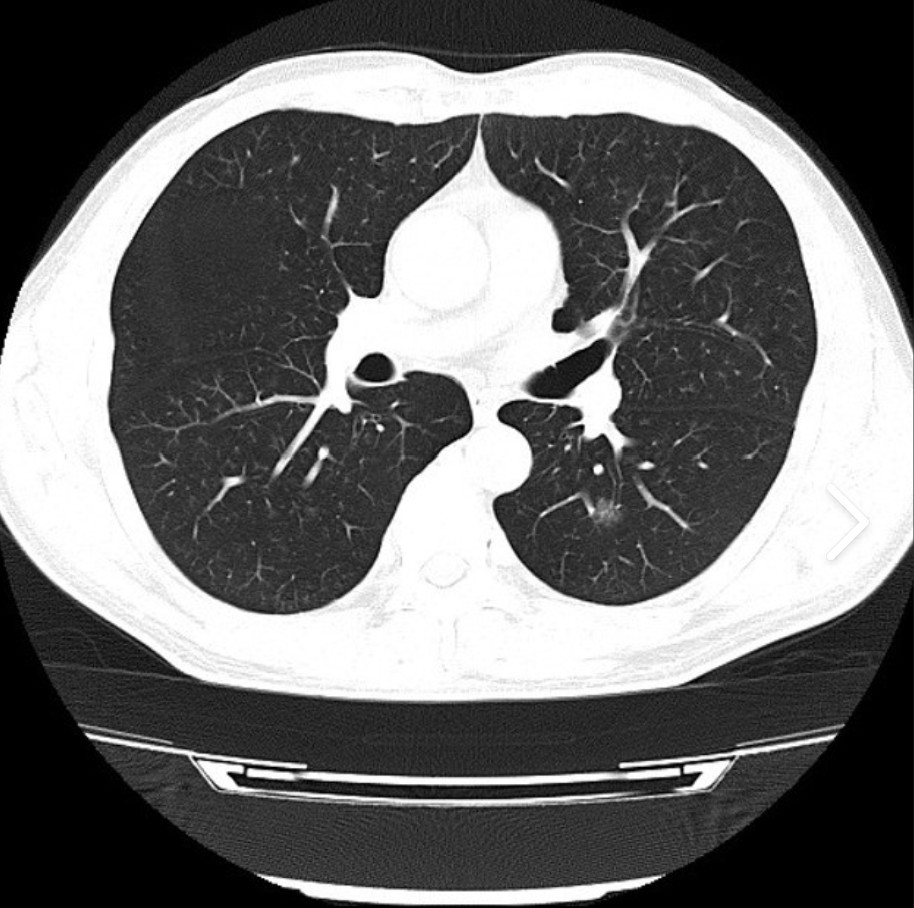

近年来,肺癌的发病率和病死率均迅速上升,目前已居所有癌症之首。随着肺癌病人数量的增加,医生对肺癌 CT 图像进行研判的工作量也增加了不少,在这种情况下,难免工作效率降低甚至会出现误诊。为了帮助医生减少重复性工作,对肺部 CT 图像进行计算机辅助检测的技术就被广泛应用于对肺癌的诊断和治疗过程中。

医学 CT 图像处理主要是研究医学图像中的器官和组织之间的关系,并进行病理性分析。因此,借助计算机及图像处理技术对 CT 图像中医生所关注的区域进行精确的分割和定位是医学图像处理的关键步骤,在临床诊断中对于协助医生进行病理研判具有重要意义。

分水岭分割是一种强有力的图像分割方法,可以有效地提取图像中我们所关注的区域。在灰度图像中使用分水岭方法可以将图像分割成不同的区域,每个区域都可能对应一个我们所关注的对象,对于这些图像的子区域可以进行进一步的处理。除此之外,使用分水岭算法还可以提取目标的轮廓等特征。

3.分水岭实现医学诊断

分水岭算法的主要目标在于找到图像的连通区域并进行分割。在实际处理过程中,如果直接以梯度图像作为输入,则容易受到噪声的干扰,产生多个分割区域;如果对原始图像进行平滑滤波处理后再进行梯度计算,则容易将某些原本独立的相邻区域合成一个区域。当然,这里的区域主要还是指图像内容变化不大或灰度值相近的连通区域。

利用分水岭对肺癌细胞进行分割诊断处理的Python代码:

实验表明,采用标记分水岭算法对肺部图像进行分割具有良好的效果,能在一定程度上突出病变区域,起到辅助医学诊断的目的,具有一定的使用价值。